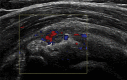

Diagnosis is crucial in decision-making when treating a patient with shoulder pain. Ultrasound is also very important in the diagnostic and therapeutic pathway, especially when surgery is being considered. This article outlines the diagnostic pathway using the patient's history, physical examination and ultrasound examination. It is important to correlate the clinical assessment with the imaging signs. It is also important to treat the patient and not the images as there may be abnormalities detected on imaging that are not symptomatic. The article covers the important diagnosis of subdeltoid subacromial bursitis, glenohumeral joint capsulitis, calcific tendinosis, acromioclavicular joint osteoarthritis and long head of biceps tendinosis. It will guide the reader in how to use the findings to treat, using ultrasound-guided injection and other techniques, including steroid injections, hydrodilatation, barbotage and extracorporeal shockwave treatment. These are discussed with the knowledge from over 30 years of experience with a literature review evidential support. I have included tips to make these procedures more effective in treatment and final outcome. There is discussion regarding the use of steroid injections in the presence of a rotator cuff tear and how to proceed if the patient has more than one disease process. The sensible use of steroids and local anesthetics are included, bearing in mind that lidocaine and high concentrations of long-acting local anesthetics are chondrotoxic and should not be injected into joints.